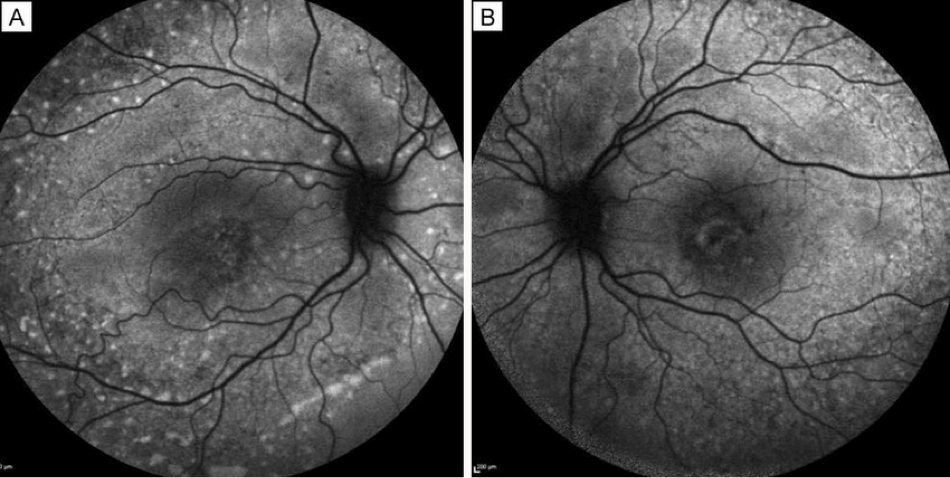

Autofluoreszenz des Augenhintergrunds (FAF)

Die Autofluoreszenz des Augenhintergrunds ist ein wichtiges bildgebendes Verfahren für die Diagnose und Überwachung der AMD, insbesondere bei fortgeschrittener trockener AMD oder geographischer Atrophie (GA).11 Ein spezielles Licht (normalerweise ein blaues) wird verwendet, um eine Autofluoreszenz eines Moleküls namens Lipofuszin hervorzurufen, das typischerweise gleichmäßig in der Netzhaut verteilt ist.8 Nicht gesunde Netzhautregionen können dunkler erscheinen, wenn es sich um atrophische Bereiche handelt, oder heller, wenn es sich um Drusen handelt. Beides sind Anzeichen für eine AMD.8,13 Das Fluoreszenzmuster kann einen Hinweis auf das potenzielle Fortschreiten der AMD bei einem Patienten geben.14